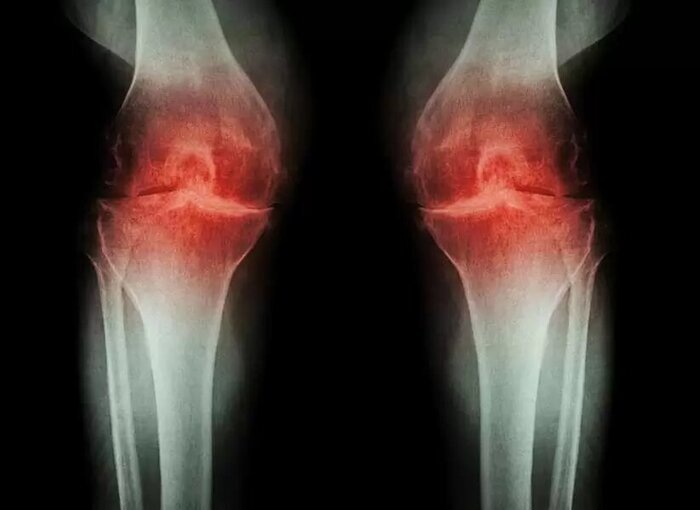

Объективно: классическая картина ревматоидного артрита с гипертрофией синовиальной оболочки сустава, эрозиями, ревматоидными узлами, единственное, не строго симметрично.

! Быстрое разрушение сустава (от появления боли до протезирования 4 года, такое бывает при длительном активном воспалительном процессе в суставе).